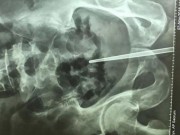

Các sĩ đang phẫu thuật lấy nhẫn ra khỏi "của quý" người đàn ông.

Các bác sĩ sau đó tiến hành làm tiểu phẫu để tháo bỏ chiếc nhẫn cưới. Trong quá trình tiểu phẫu, các bác sĩ nhận thấy có rất ít khoảng hở để tháo nhẫn. Chính vì thế họ đã chích vào "của quý" để làm giảm bớt máu tụ.

“Bác sĩ phải dùng ống tiêm 20 ml và kim hồng để thực hiện việc chích máu tụ. Chỗ sưng tấy sau đó bị xẹp đi và chiếc nhẫn được lấy ra thành công”, tạp chí y tế Nam Phi cho biết.